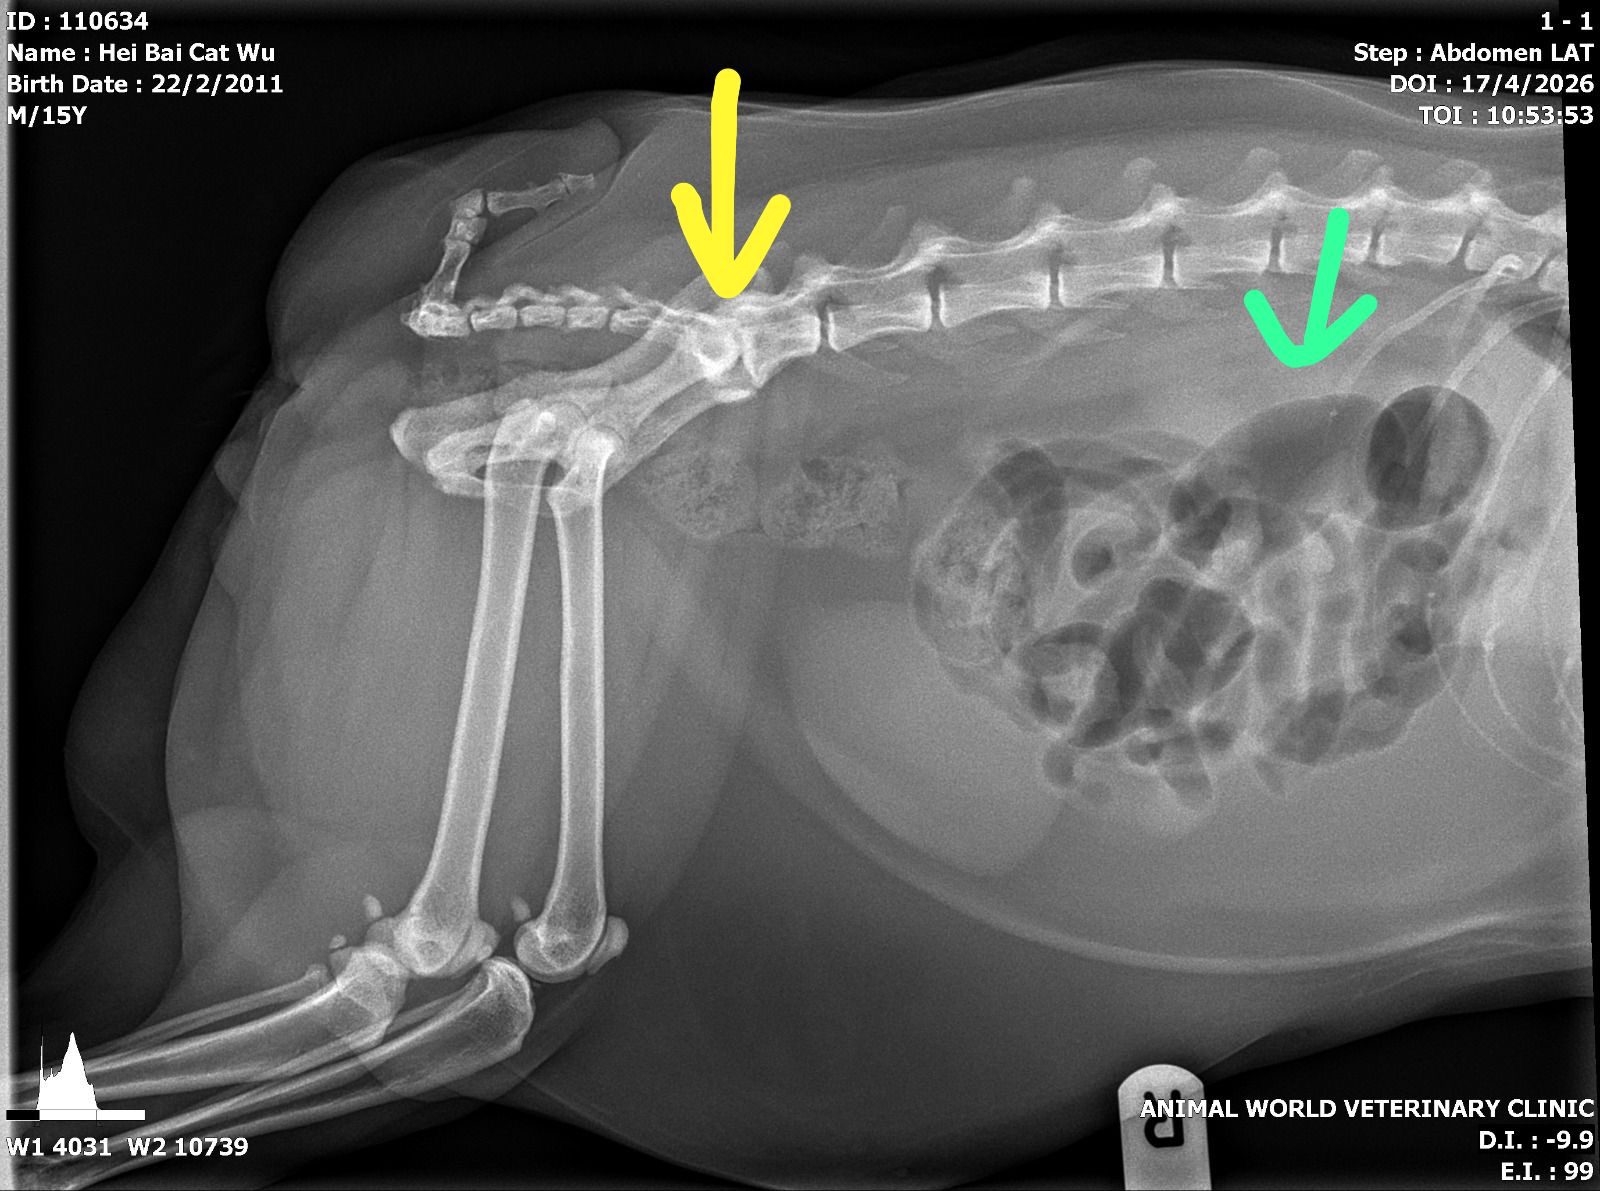

“Green arrow – dilated loop of gut, either gassy colon or SI bt need VD to confirm

Yellow arrow – area of bright white ie sclerosis could be lower back/pelvis area arthritis, monitor for any dragging of backpaws in case of nerve pinching”

11.04am: n:”did a quick lateral abdo since we’re in that position for backleg xrays, no bladder stones seen, also did a quick bladder scan – confirm no stone inside bladder. melox is injection or oral u have? no need bupre for now unless still painful but would prefer gaba over bupre. no need antibiotics” – I’ll prep meloxicam inj n oral tmr, ill give jab and let jo/mmm help oral if I’m not in. GABA they can give tmr I’ll prep. Today he covered by methadone.